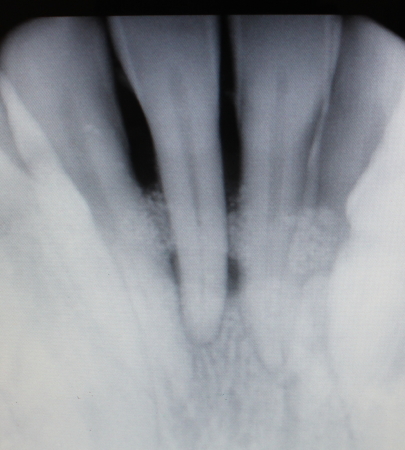

オペ前のレントゲン写真